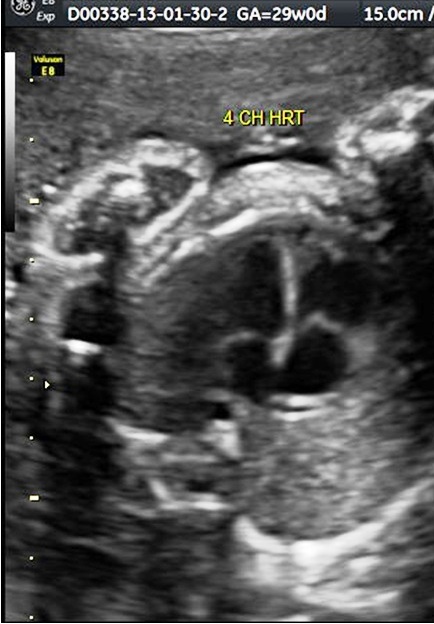

Fetal Echocardiography

A detailed study of the fetal heart is indicated if either the mother or father or a previous child has congenital heart disease, or if the mother has diabetes, or if the mother has been on certain medications (eg. many anti-epileptic drugs), or if the ultrasound scan shows some extra- cardiac or cardiac anomaly in the fetus. We are not only one of the few referral Centres for fetal Echocardiography, but also conduct training in this subject.